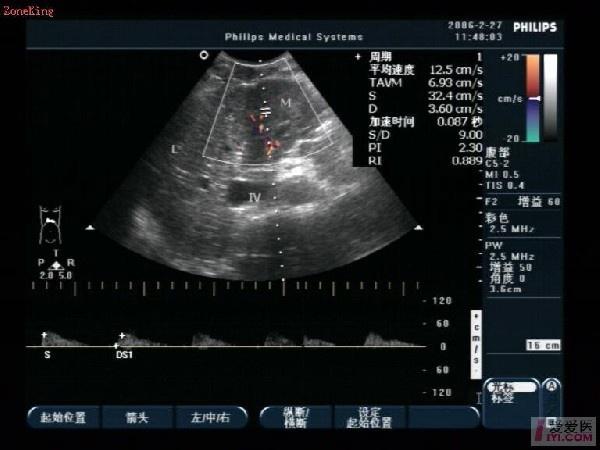

肝脏:右叶斜径约125mm,包膜欠光滑,肝静脉清晰,实质回声欠均质,肝左叶探及约42mm×35mm中等偏低回声,边界尚清,边缘欠规则,其内回声欠均匀,CDFI:包块内及周边加彩填色可见少许树枝状彩色血流信号,PW:其中一支动脉:RI:0.88,PSV:32.4cm/s;门静脉内径13 mm,出肝门大量气体干扰显示欠清。

请问血流阻力很高,是不是可以往CA的方向靠靠呢?这个病人过几天还来复查!

肝左叶探及约42mm×35mm中等偏低回声,牵拉包膜,引起腹痛,回声不均质,并且RI:0.88,PSV:32.4cm/s;占位改变最大,门静脉内径13 mm,不算很宽,正常可以考虑1.4CM,作为参考值,内部回声不是很清楚。符合肝实质内占位性超声改变